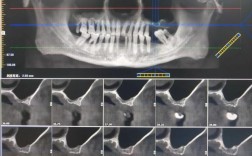

诊断与风险评估的精细化锥形束CT(CBCT)的普及与标准化应用:核心进展:CBCT已成为评估上颌窦与牙根关系的金标准,它提供三维立体图像,清晰显示:上颌窦底形态(平坦、凹陷、气化程度),牙根与窦底的距离(关键指标),牙根是否已穿入窦腔(穿...